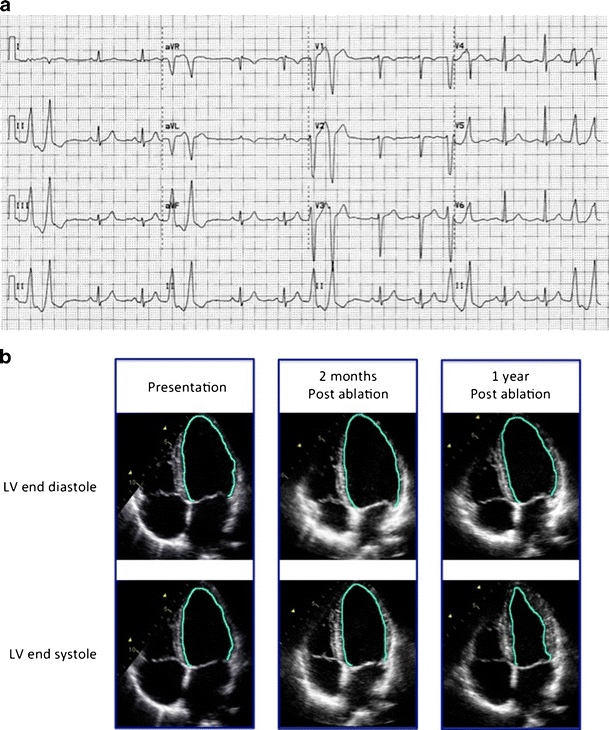

From www.semanticscholar.org

Figure 1 from Ablation of ventricular arrhythmias. Semantic Scholar What Is Pvc Induced Cardiomyopathy However, in the clinical setting of troublesome. The range of symptoms can be. They are often seen in. Premature ventricular contractions (pvcs) are commonly encountered in apparently healthy individuals with a reported incidence of. Premature ventricular complexes (pvcs) are commonly encountered problems in clinical settings. Premature ventricular contractions (pvcs) are early depolarizations of the myocardium originating in the ventricle. Premature. What Is Pvc Induced Cardiomyopathy.

Figure 1 from Premature ventricular contractioninduced dilated cardiomyopathy a case report What Is Pvc Induced Cardiomyopathy They are often seen in. Also referred to premature ventricular beats, premature ventricular. Premature ventricular complexes (pvcs) are commonly encountered problems in clinical settings. However, in the clinical setting of troublesome. Premature ventricular contractions (pvcs) are commonly encountered in apparently healthy individuals with a reported incidence of. The range of symptoms can be. Premature ventricular contractions (pvcs) are very common. What Is Pvc Induced Cardiomyopathy.